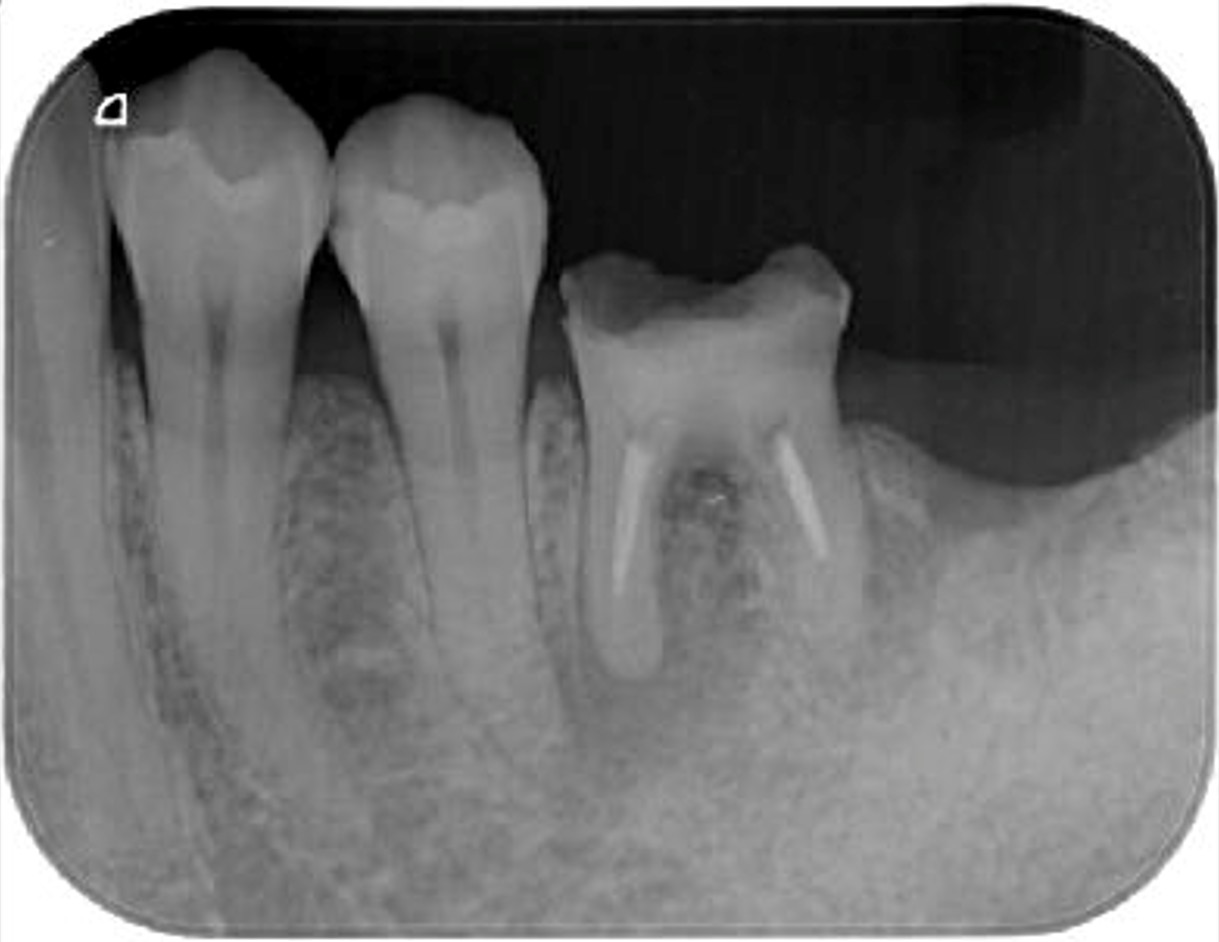

症例1

| 患者様データ | 30代 女性 |

| 来院時の主訴 | 「左下の歯グキが腫れてきた。」 |

| 医院の診断 | 慢性根尖性歯周炎、歯根破折 |